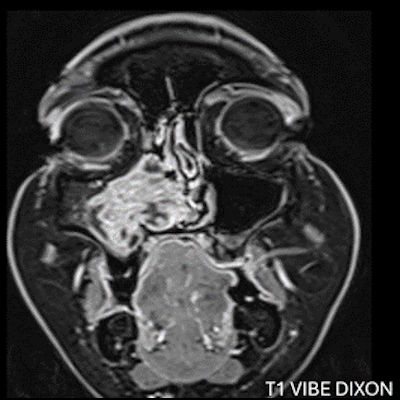

- A) Koronal T2 ağırlıklı görüntülerde sol maksiller sinüs lümenini dolduran, belirgin ‘convoluted’ (karmaşık-kıvrımlı) serebriform patern sergileyen lezyon (oklar), kontrastlı seride heterojen ve yoğun kontrastlanma göstermektedir (oklar). Perfüzyon incelemesinde pedinkülünde perfüzyon artışı gösterdiği, diğer kontrastlanan segmentlerin nispeten hipoperfüze olduğu görülmektedir (ok).

- MR incelemesinde sinonazal inverted papilloma tipik olarak T2 ve post-kontrast T1 serilerde ‘convoluted’ serebriform paternde heterojen sinyal ve kontrastlanma gösteren, pedinküler orijininde daha belirgin perfüzyon artışı sergileyen, genellikle difüzyon kısıtlaması izlenmeyen ve komşu sinüs duvarlarında ekspansiyona bağlı remodelinge yol açabilen benign ancak lokal agresif karakterde bir yumuşak doku kitlesi olarak izlenir.